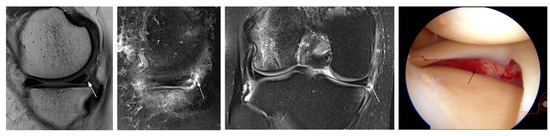

3.1. Unavoidable Errors

| FP MM | ||||||

| 7 | F, 46 y | 39 | root tear posterior horn | normal | ||

| 8 | F, 36 y | 18 | ramp lesion posterior horn | normal | acute | |

| 6 | M, 18 y | 25 | ramp lesion posterior horn | normal | acute | |

| 9 | M, 50 y | 10 | tear posterior horn PO remnant | intact stable PO remnant | ||

| 10 | M, 25 y | 11 | ramp lesion posterior horn | normal | acute | |

| 11 | M, 34 y | 8 | ramp lesion posterior horn | normal | acute | |

| 12 | M, 25 y | 24 | ramp lesion posterior horn | normal | acute | |

| 13 | F, 40 y | 50 | tear posterior horn PO remnant | intact stable PO remnant | ||